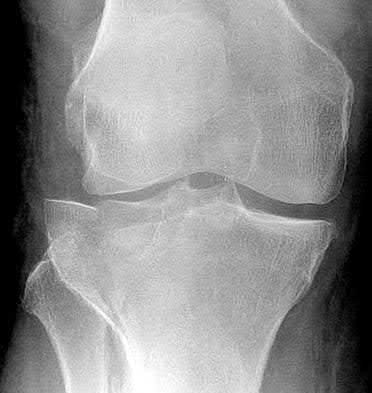

1. # A 32-year-old male sustains the injury shown in Figure A and undergoes treatment as shown in Figure B. Following placement of this implant, what is the best technique to confirm it is not too proud proximally?

1. Lateral radiograph of the knee

2. AP radiograph of the knee

3. Oblique radiographs of the knee

4. Merchant radiograph of the knee

5. Internally rotated 45 degree view of the knee Corrent answer: 1

The safe zone for tibial nail placement as seen on radiographs is just medial to the lateral tibial spine on the anteroposterior radiograph and immediately adjacent and anterior to the articular surface as visualized on the lateral radiograph.

Tornetta et al specifically located the safe zone for nail entry in a study using fresh frozen cadaver knees. The authors found that the safe zone for nail placement is located 9.1+/-5 millimeters lateral to the midline of the plateau and three millimeters lateral to the center of the tibial tubercle. The width of the safe zone averaged 22.9 millimeters and was as narrow as 12.6 millimeters.

The starting point of the of the nail can be best viewed on the lateral knee radiograph, an example of which is shown in Illustration A. Illustration B shows the "sweet spot" for nail insertion as defined by Tornetta.